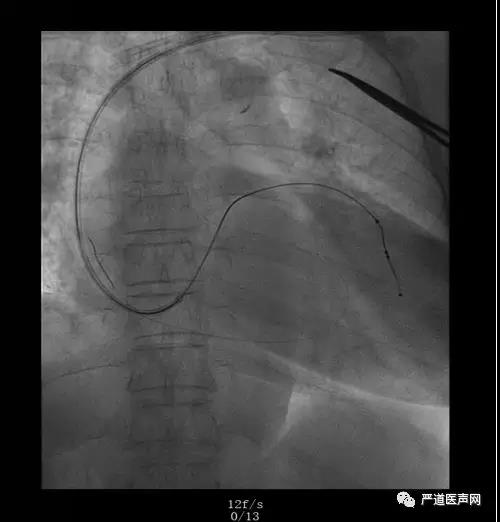

病例七

病例八